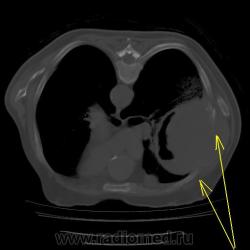

Правое легкое: в проекции средней доли (S3,4,5) определяется объемное образование преимущественно однородной структуры с ровными, четкми контурами размерами 92х88х94мм. Плотность его составляет 19-25 едН. В медиальных отделах образования содержится серповидная полоска воздуха. Латеральные отделы образования выходят за контуры грудной полости на 42 мм. На этом участке ребра не дифференцируются. Внутренний контур передней зубчатой, подлопаточной мышц размытый, граница между образованием и ними отчетливо не видна. Кзади от образования, в кортикальных отделах в легочной ткани инфильтрация. Кпереди от описанного образования расположен участок, широким основанием прилежащий к грудной стенке, имеющий плотность 12-20 ед.Н, однородную структуру, размеры 14х48мм. Прилежащее ребро интактно.